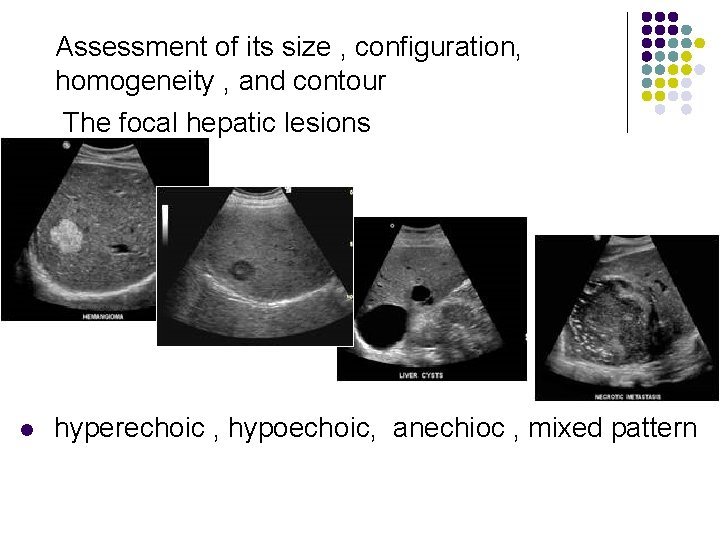

Pathology of the Live l Evaluation of the liver parenchyma includes the assessment of its size , configuration, homogeneity , and contour.

Assessment of its size , configuration, homogeneity , and contour

Assessment of its size , configuration, homogeneity , and contour The focal hepatic lesions l hyperechoic , hypoechoic, anechioc , mixed pattern